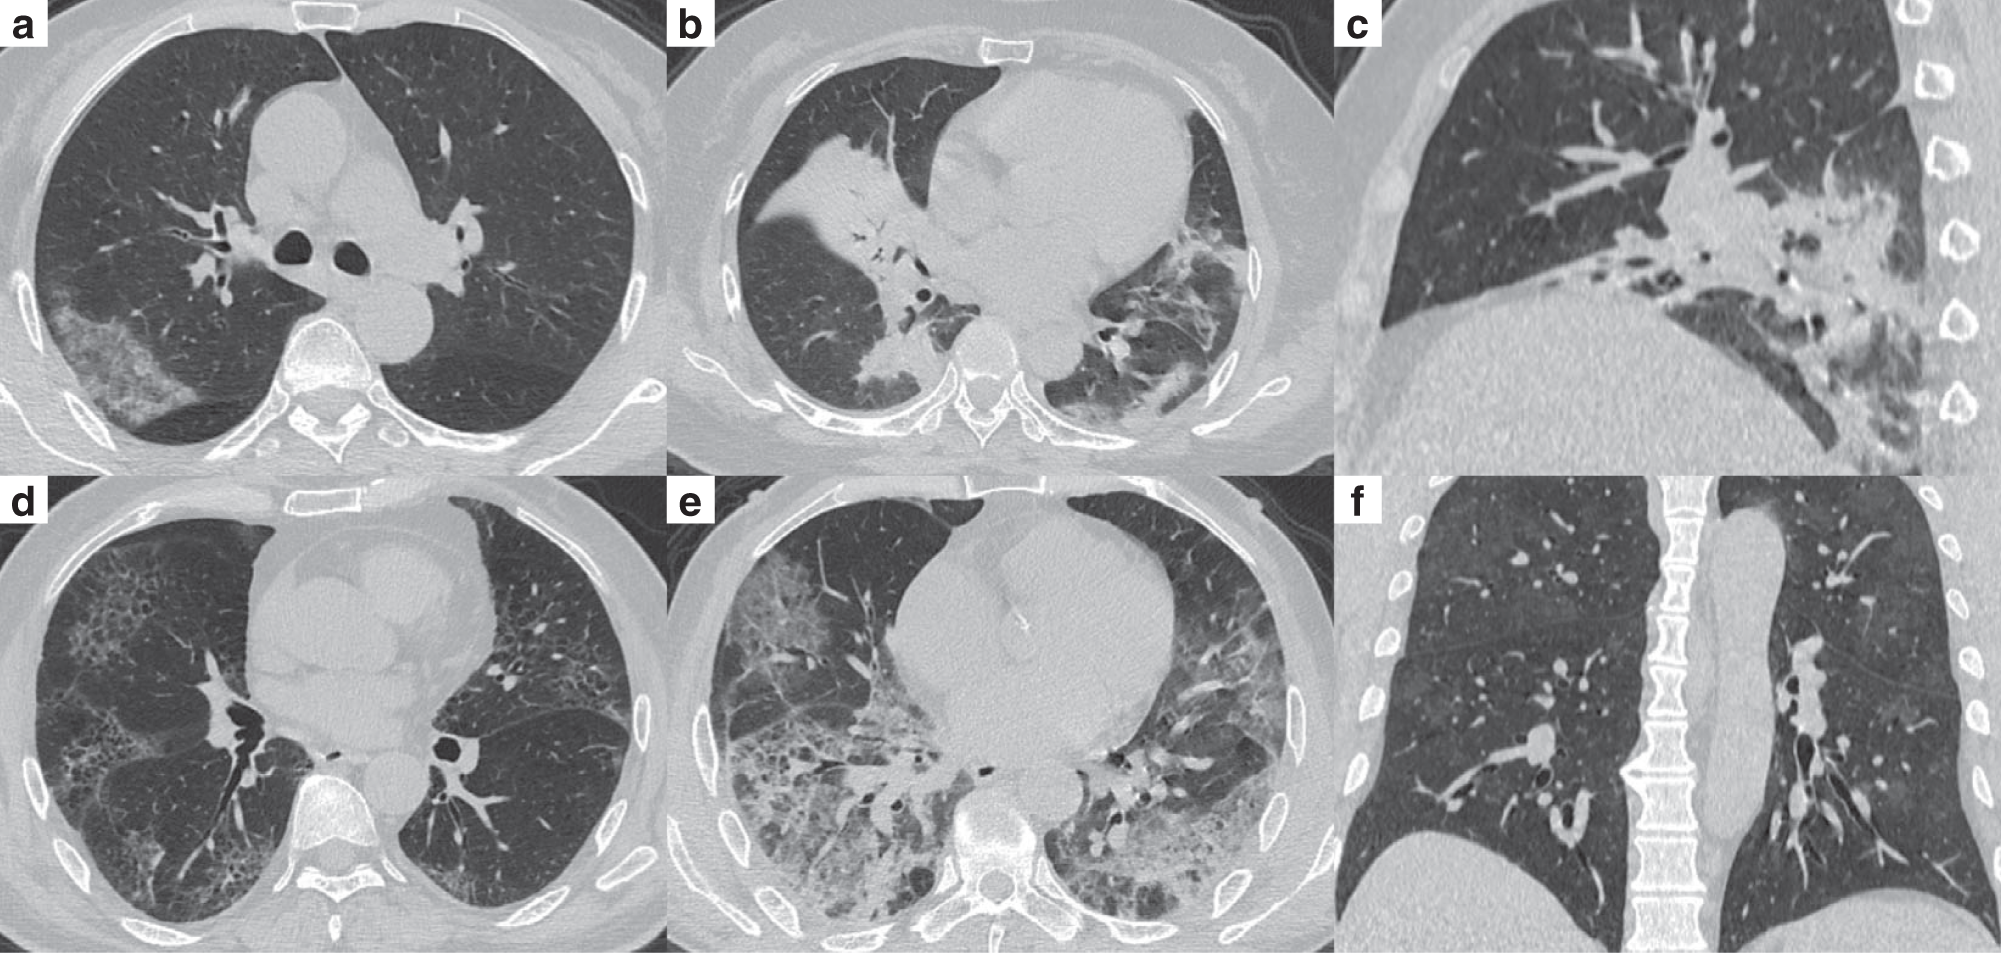

Fig. 2: Representative chest CT images of patients with COVID-19 pneumonia.

a Subpleural patchy areas of GGO with crazy-paving sign in the right middle lobe. b Multiple patchy areas of consolidation in the right middle lobe, left upper lobe, and bilateral lower lobes and air bronchogram in the right middle lobe. c Multiple patchy areas of organizing pneumonia in the right middle and lower lobes on the sagittal image with CT severity score of 9 for the right lung. d Bilateral and peripheral multiple patchy areas of GGO with reticular and intralobular septal thickening. e Multiple mixed distributed pure GGO, GGO with consolidation, and interlobular septal thickening in bilateral lungs. f Bilateral multiple patchy and thin areas of GGO in the posterior parts of the lungs.